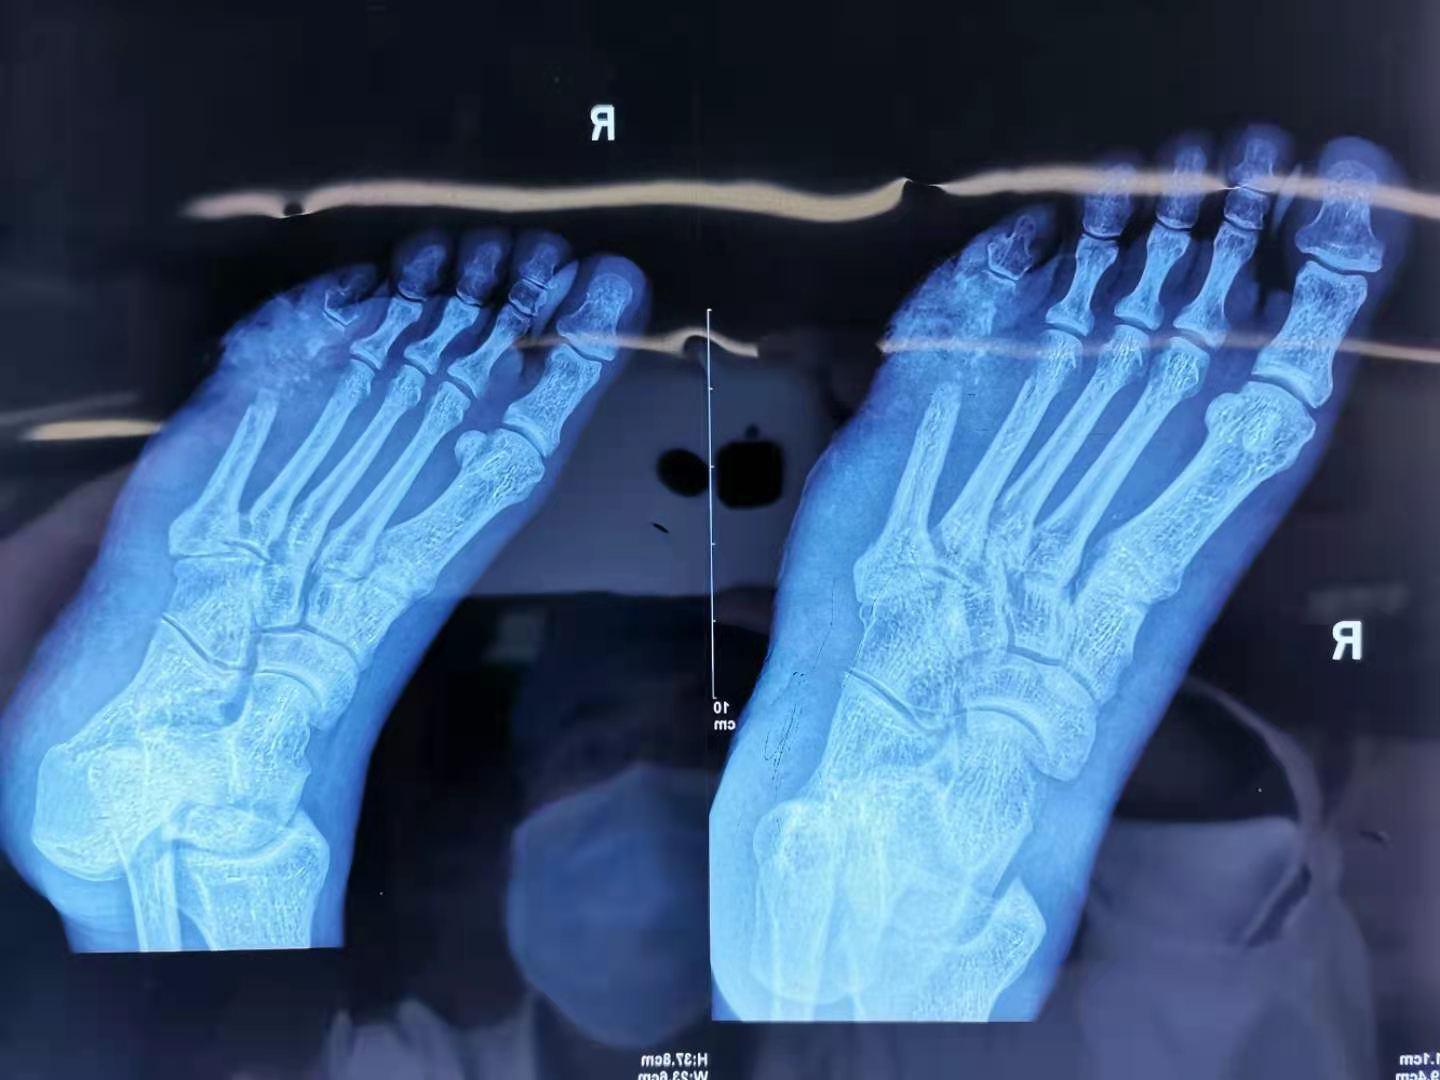

患者长期糖尿病,右足部出现溃烂、坏死

X线显示右足部骨坏死